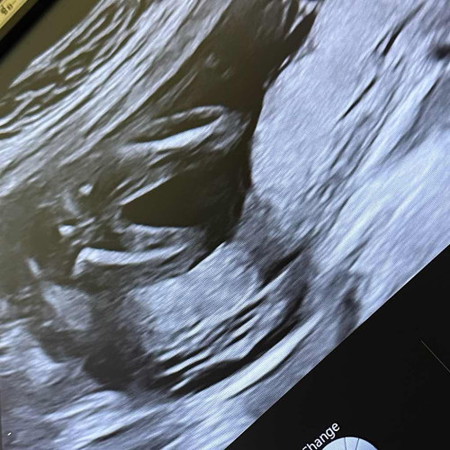

ใครพอจะดูออกบ้างค่ะ? ว่าเพศอะไรค่ะ แต่คุณหมอเดาว่าได้ลูกสาวค่ะ แม่ๆคนไหนดูเป็นบ้างค่ะ

แม่ๆช่วยดูให้หน่อยค่ะว่าได้ ลูกสาวแน่มั้ยค่ะ😂

น่าจะ ญ นะคะ ช่วงหว่างขาน้องไม่มีอะไรยื่นออกมา ของเรา ช มียื่นจู๋น้อยออกมาให้เห็นเลยคะ

มองเป็นผู้หญิงค่ะ บ้านนี้ก็เป็นภาพแบบนี้เลยหมอบอกหญิง90%

ผู้หญิงค่ะ แฮมเบอรเกอรชัดเลย